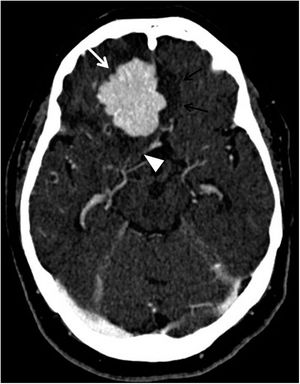

Los resultados de las TC por traumatismo se encuentran resumidos en la tabla 2. En la figura 2 se muestra uno de los casos con combinación de patología traumática aguda recogidos en la tabla 2.

Tomografía computarizada de cráneo basal, plano axial. Paciente con traumatismo craneoencefálico que presenta hematomas de partes blandas parietal izquierdo (punta de flecha blanca) y frontal derecho (punta de flecha negra), hematoma subdural agudo en la convexidad izquierda (triple flecha negra), con áreas de menor densidad en su interior, en relación con sangrado hiperagudo (asterisco blanco), que condiciona desviación de la línea media hacia la derecha (doble flecha blanca), contusión hemorrágica frontotemporal derecha (asterisco negro) y hemorragia subaracnoidea (flecha blanca).